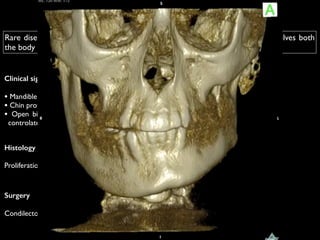

Rare disease that results from unilateral excessive growth of the mandible, involves both

the body and ramus of mandible and leads to facial asymmetry

Clinical signs

!

• Mandible deviation to the opposite side

• Chin protrusion

• Open bite on the affected side and cross bite in the

controlateral side

Surgery

Condilectomy of the affected side